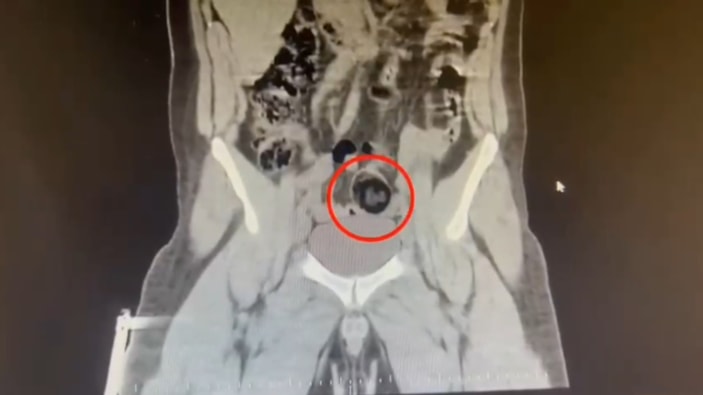

Şüpheli hareketler sergileyen kuryenin, götürüldüğü hastanede yapılan iç beden muayenesinde makatında cisim olduğu anlaşıldı.

MAKATINDAN 105 GRAM UYUŞTURUCU ÇIKTI

Kuryenin makatındaki 105,98 gram metamfetamin, gerçekleştirilen cerrahi müdahaleyle çıkarıldı.